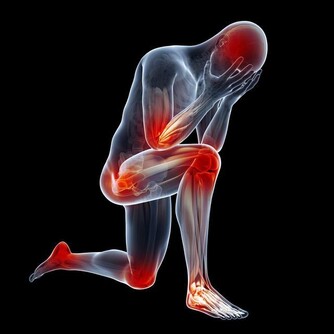

*****5.胸口疼痛小心冠心病*****

2016年,互聯網企業高管猝死事件頻發,前有天涯社區副主編金波,後有春雨醫生的創始人張銳,從這些由于冠心病猝死的報導,可以發現很多患者是在劇烈運動或者重體力勞動後會出現胸口的疼痛的症狀。

這種情況很多人不在意,殊不知這正是冠心病的早期症狀。

如果能夠及早重視,配合醫生的治療,這種情況是完全可以延緩,甚至停止疾病的發展。